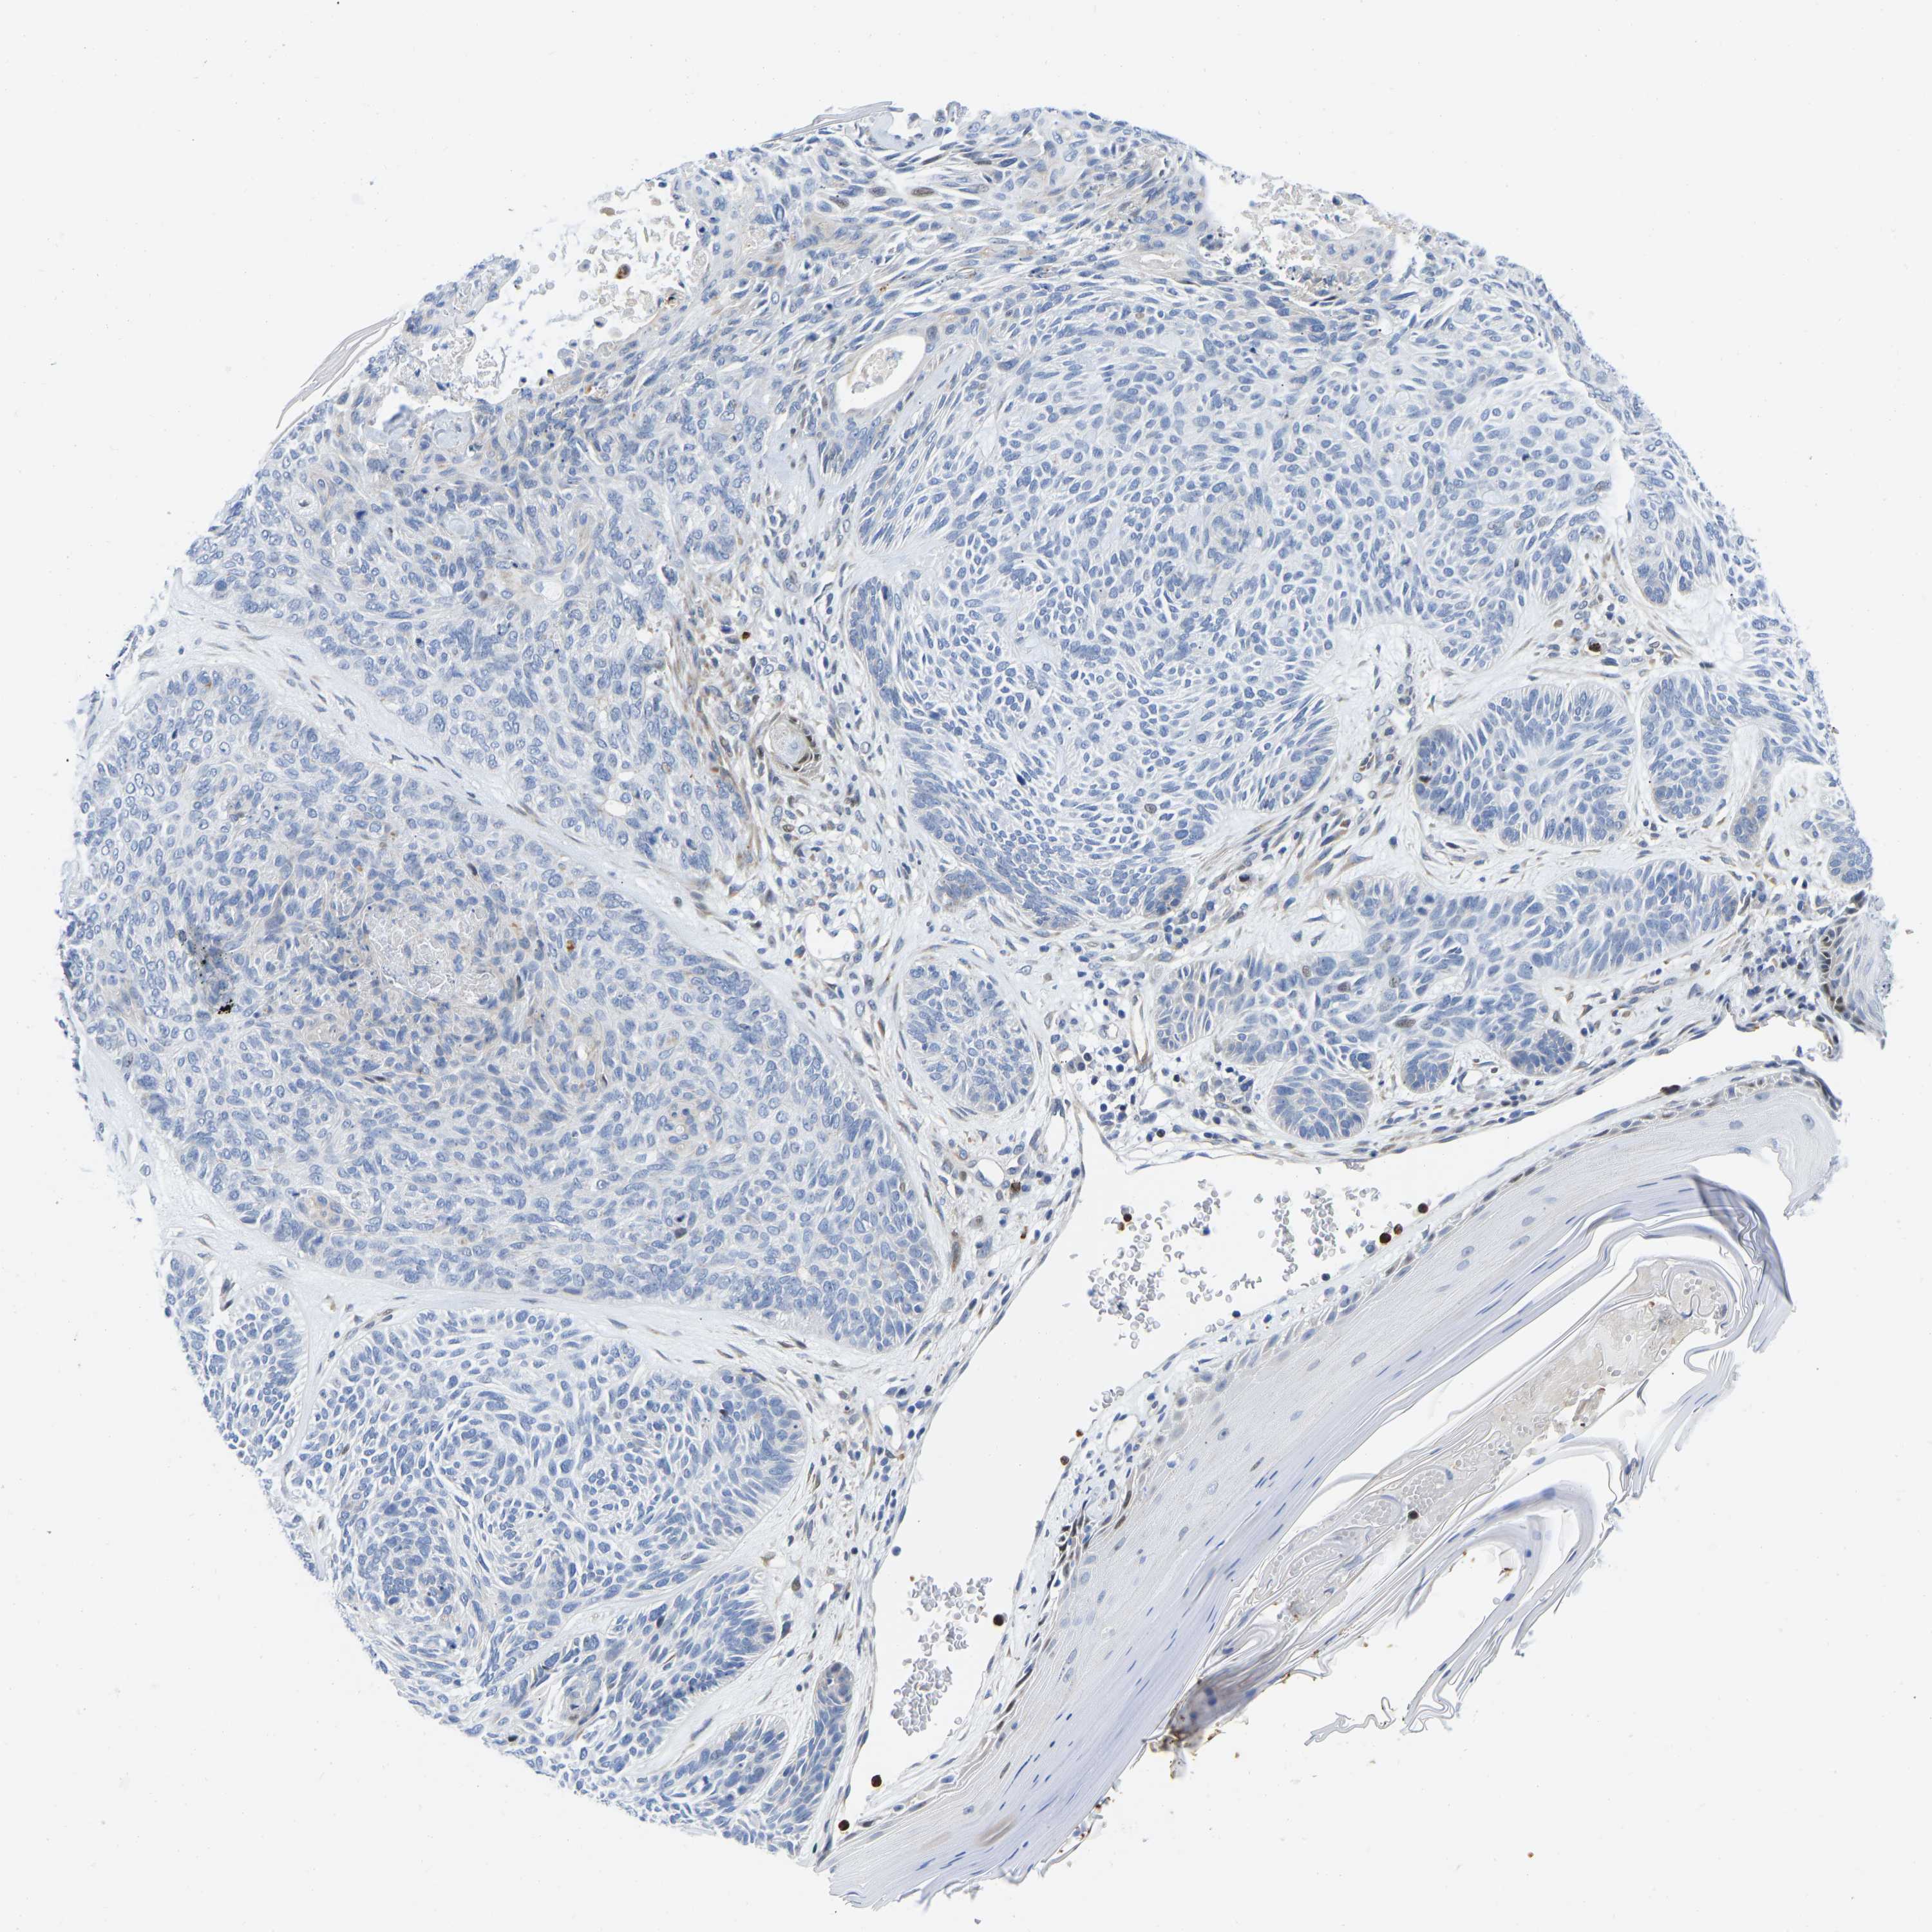

SKIN CANCER - Protein expressioni

A mouse-over function shows sample information and annotation data. Click on an image to view it in a full screen mode. Samples can be filtered based on level of antibody staining by selecting one or several of the following categories: high, medium, low and not detected. The assay and annotation is described here.

Antibody stainingi

Antibody staining in the annotated cell types in the current human tissue is reported as not detected, low, medium, or high, based on conventional immunohistochemistry profiling in selected tissues. This score is based on the combination of the staining intensity and fraction of stained cells.

Each image is clickable and will lead to virtual microscopy that enables deeper exploration of all samples and also displays staining intensity scores, fraction scores and subcellular localization as well as patient and tissue information for each sample.

Antibody HPA076420

Squamous cell carcinoma, NOS